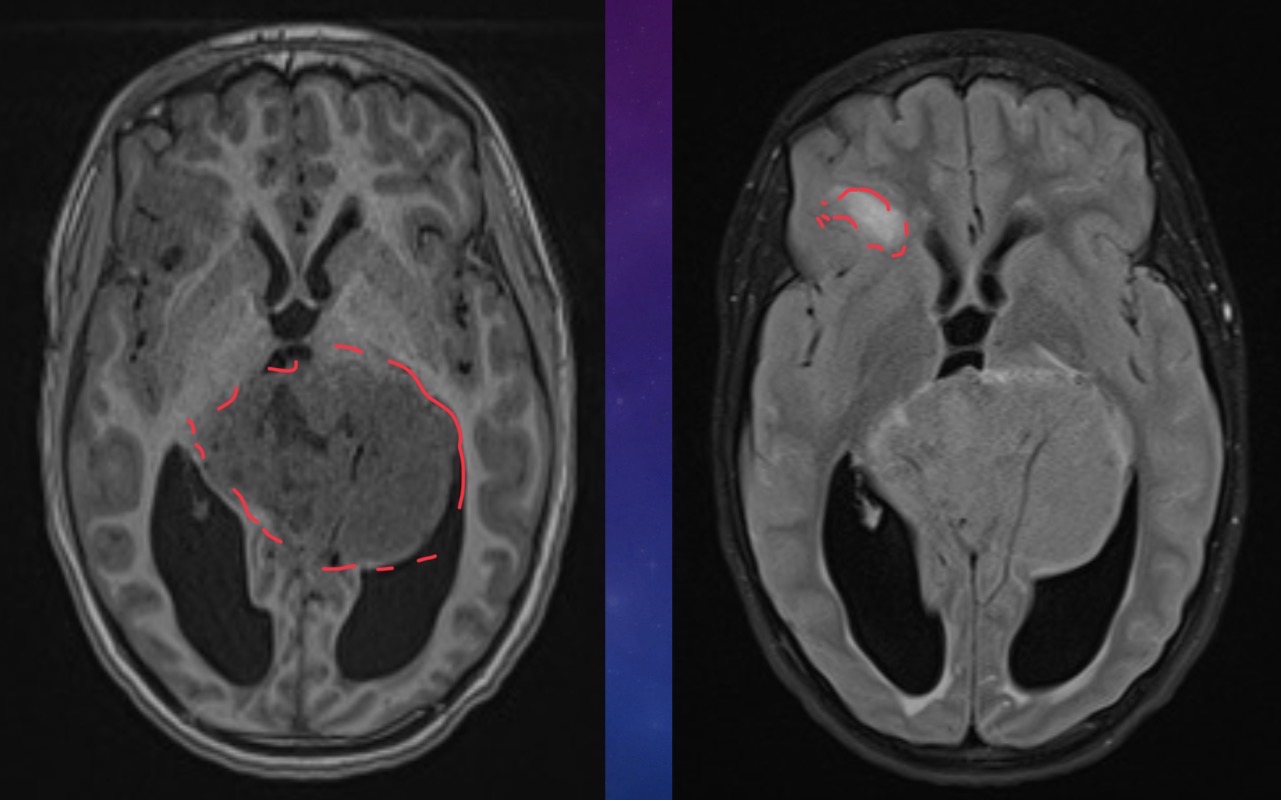

55-year-old female presents with occipital headaches and neck stiffness

Thrombosed Aneurysm of postero-inferior cerebellar artery

55 year-old male is following up with neurosurgery for a pre op scan

Spoke wheel sign = meningioma